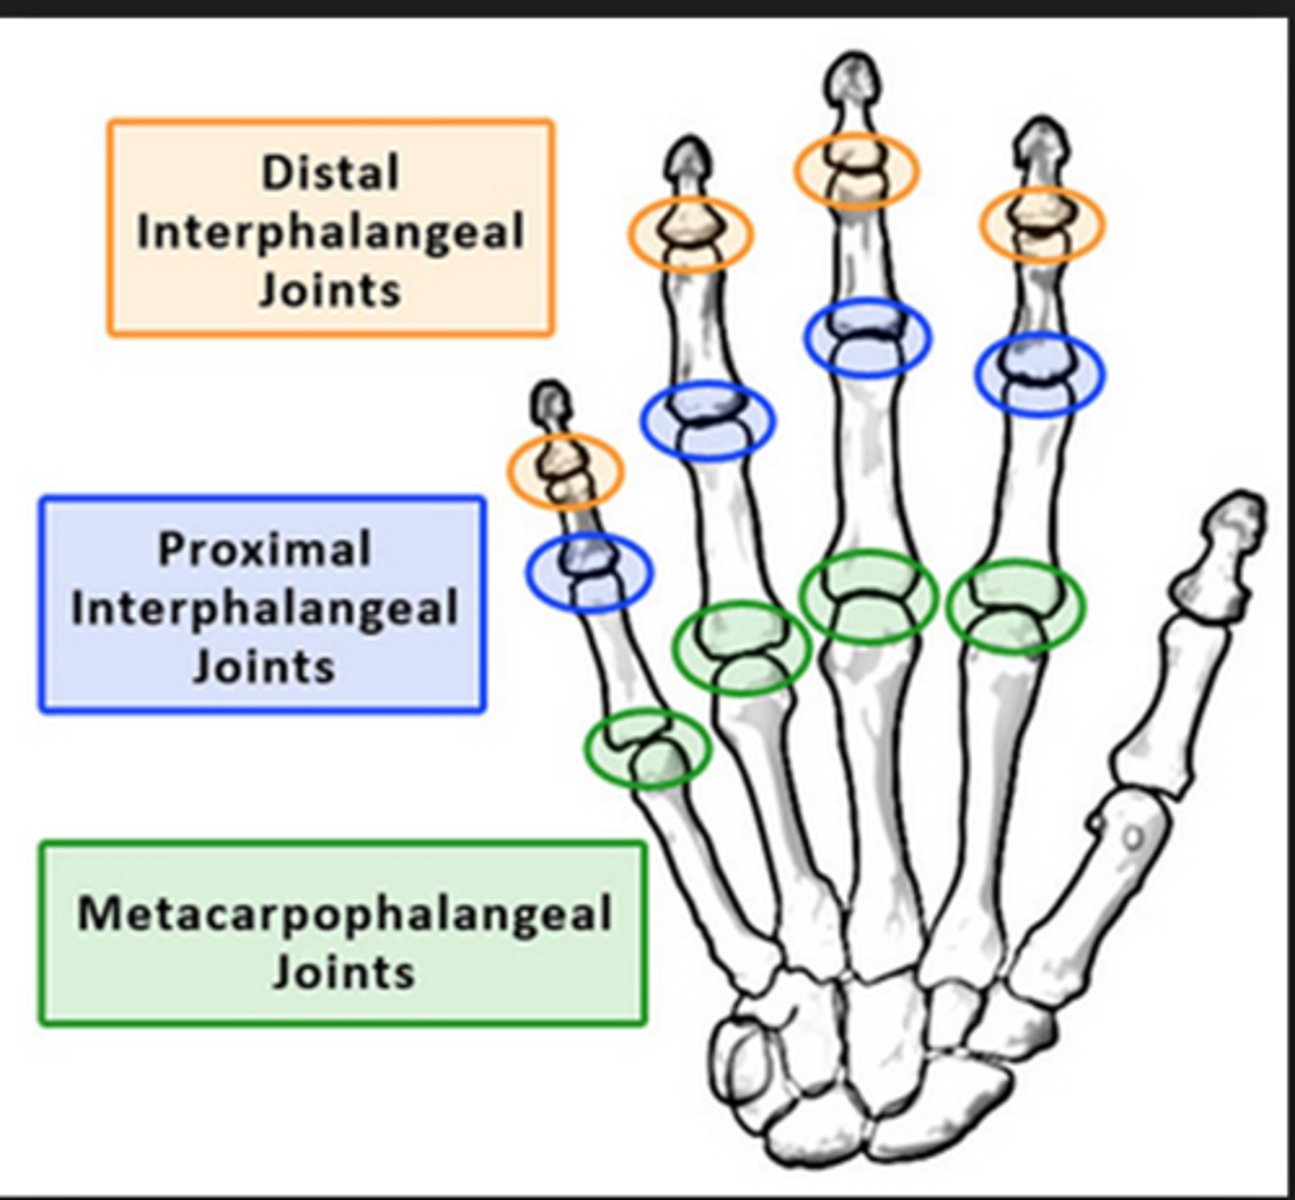

Metacarpophalangeal joints

knuckles; where heads of carpal bones articulate with the proximal phalanges of digits

Proximal interphalangeal joints

between proximal and middle phalanges

Distal interphalangeal joints

Joints between middle and distal phalanges.